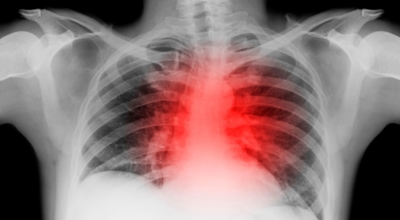

왼쪽 갈비뼈 아래 통증 - 흉막염

흉막염은 익숙치 않은 병명인데요, 폐를 덮고있는 조직에 염증이 발생하는 질환을 말해요. 흉막염은 대개 폐의 혈전과 연관된 박테리아, 바이러스 또는 진균성 폐렴, 악성 종양, 외상 또는 폐경색의 결과로 일어날 수 있답니다. 왼쪽 흉막염은 왼쪽 흉곽 아래쪽에 통증을 나타나게 할 수 있지만 이것의 주요 증상은 숨을 쉴 때 날카 롭고 찌르는듯한 통증입니다. 호흡 중에 심한 흉통이 있으면 병원에 방문하여 진료를 받아야 해요.